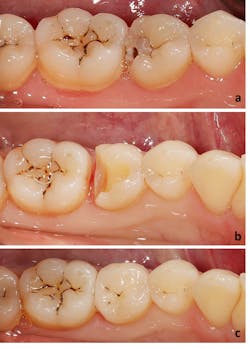

For partial coverage restorations, defect-specific tooth preparations removed all the caries and created proper retention form. Inlay or onlay partial coverage preparation design was then chosen based on the remaining tooth structure.1 The complete coverage restorations were approximately 1.2 mm in depth, and marginal finishing burs were employed.

The restorations

After clinical evaluation and necessary adjustment, all restorations were etched (4.5% buffered hydrofluoric acid, IPS Ceramic Etching Gel; Ivoclar Vivadent) for 20 seconds, and silane (Monobond Plus; Ivoclar Vivadent) was applied for 60 seconds. The teeth were etched with 38% phosphoric acid (Etch-Rite; Pulpdent), coated with a desensitizer (Gluma Desensitizer; Kulzer), and dentin bonded (Excite; Ivoclar Vivadent). The restorations were adhesively luted with a light-polymerizing resin (Variolink II; Ivoclar Vivadent) activated with an LED polymerization light (Bluephase Style; Ivoclar Vivadent). All the excess cement was removed thoroughly.

Prior to cementation, the following parameters were entered or determined: type of ceramics, type of restoration, restoration thickness measured by calipers at up to seven points (mesial, distal, buccal, lingual, mesial-occlusal, midocclusal, distal-occlusal), tooth position, age and sex of the patient. The restorations with at least one of the above-described measurement points less than 1 mm were grouped in the thickness of less than 1 mm.